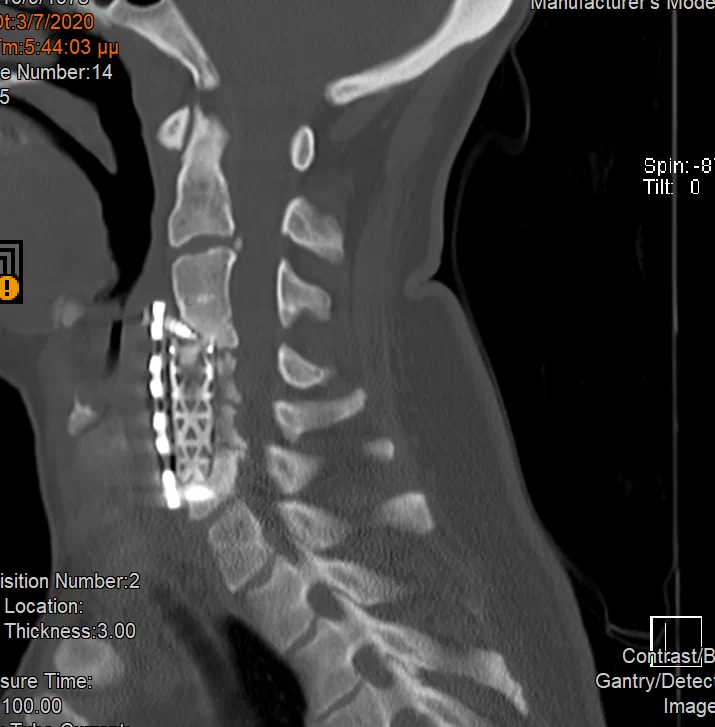

Ψευδάρθρωση μετά από σωματεκτομή Α5 & Α6 – Σπονδυλοδεσία ΑΜΣΣ 360ο

Ασθενής γυναίκα 43 ετών με ιδιαίτερα έντονο άλγος αυχένα και δεξιού άνω άκρου (κατανομής κυρίως Α7 ρίζας). Συνοδός ζάλη, τάση προς έμετο και δυσφαγία. Ο